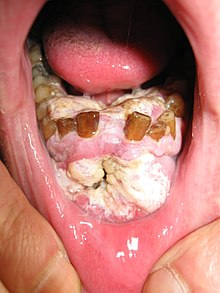

Dr. Anupam Chanda

RESEARCH CONTRIBUTIONS ON ORAL CANCER IN INDIA: A SCIENTOMETRIC ANALYSIS